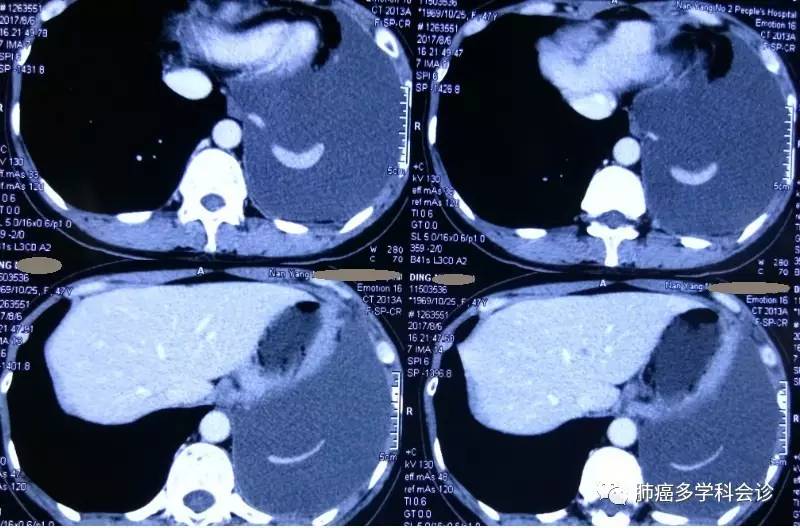

患者丁MH,女,47岁。2017年4月因咳痰、胸闷在当地医院行CT检查,发现左肺上叶占位性病变、左侧大量胸腔积液、纵膈及左侧腋窝淋巴结肿大。超声提示双侧颈部异常淋巴结,考虑转移。

2017.06.08 复查CT:左肺肿块稍缩小,左侧胸腔积液量增多,胸骨、左侧肱骨头、部分胸、腰椎骨质改变,考虑骨转移。SPECT进一步证实全身多发骨转移;

2017.08复查CT:较前变化不大。脑MRI未见转移灶。

2017.08.06复查CT如下: